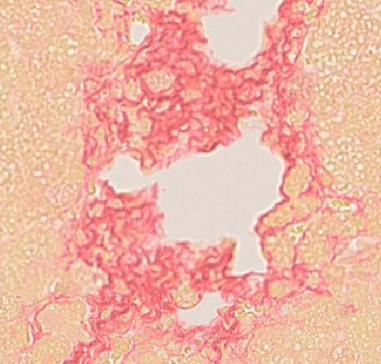

目标物定量

面积定量